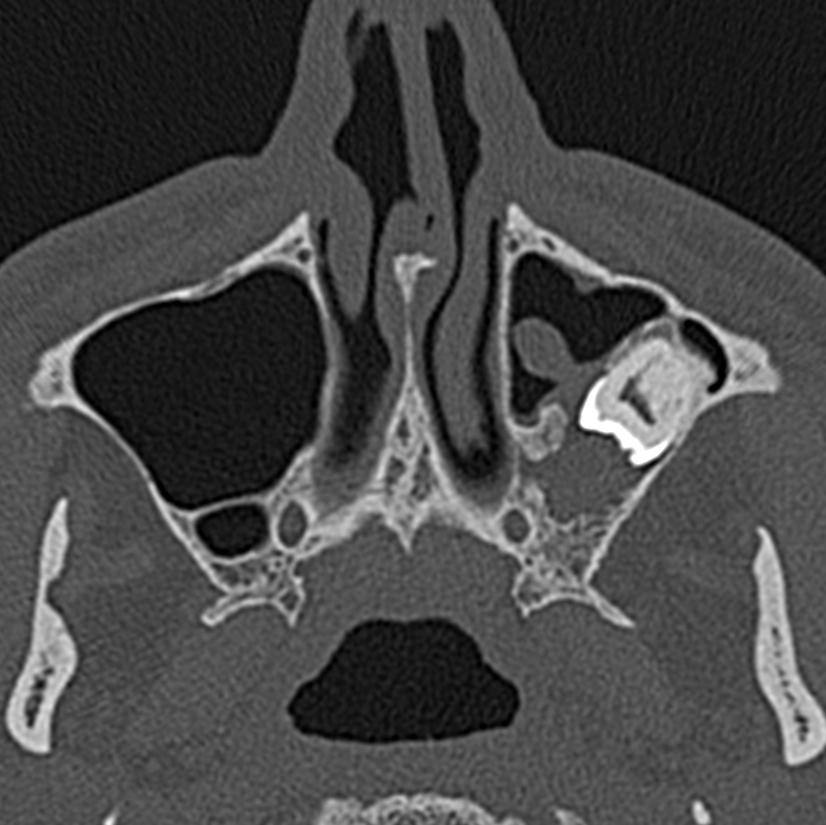

Предоперационная панорамная рентгенограмма мужчины 46 лет. Высота остаточной кости составляет около 2–3 мм, рентгеноконтрастность синуса наблюдается в правой верхней челюсти

Рис. 2Предоперационная КТ PNS. В правой верхнечелюстной пазухе наблюдается куполообразная рентгеноконтрастность

Диагноз слизистой ретенционной кисты установлен на основании рентгенограммы и аспирации слизи из оболочки верхнечелюстной пазухи во время операции. Клинико-рентгенологический признак в диагностике заболевания следующий [6]:

На рентгенограмме они чаще всего наблюдаются в виде куполообразных рентгеноконтрастных образований на дне верхнечелюстной пазухи.